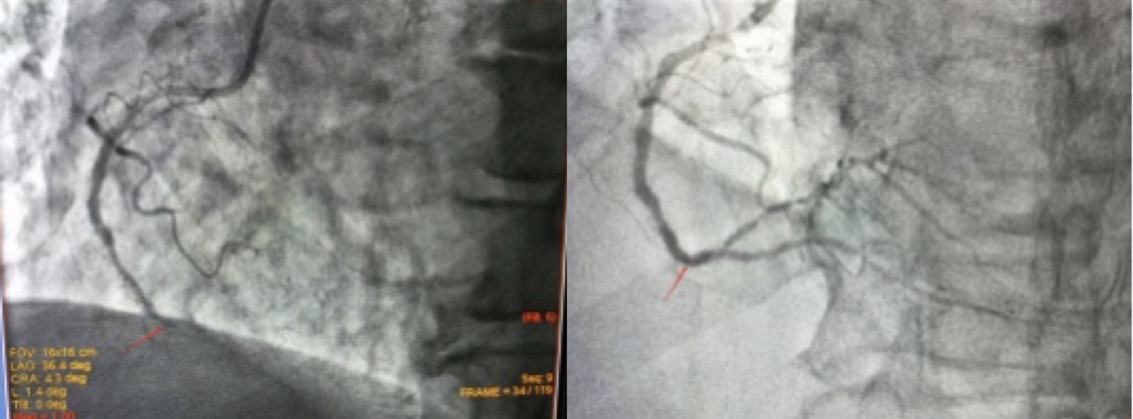

丁大爷入院后,心内科一病区医生对其进行了详细的病情评估,初步诊断为“急性非ST段抬高型心肌梗死”,在征得患者及家属同意后,于10月27日为丁大爷行冠脉造影检查,结果显示:前降支近中段节段性偏心狭窄最重60%,回旋支细小,血流通畅,均达TIMI3级;但右冠脉远段支架内闭塞,血流TIMI0级。心内科介入团队面对患者冠心病诊断明确,曾行支架植入治疗,现反复心绞痛发作,造影提示支架内完全闭塞,且管腔细,即使再次植入小直径支架,仍然增加再狭窄几率,且患者高龄,再次支架植入需更强的抗血小板方案,疗程至少1年,增加出血事件几率等情况,经反复讨论,最终考虑使用药物球囊扩张治疗,使闭塞段血管恢复有效管腔面积和正常血流,并减少再狭窄几率,既达到治疗目的,同时又可以缩短双联抗血小板时间,在一定程度上降低出血事件发生率。经过和患者及家属的充分沟通,患方接受此种治疗方案,并积极配合治疗。手术由心内一病区主任冯天保、主诊医师李文辉共同完成,右冠开通后经过充分预处理,后送入2.5mm*30mm药物球囊扩张30s,复查冠脉造影右冠管腔恢复,血流恢复正常,手术过程顺利,患者无不适主诉。